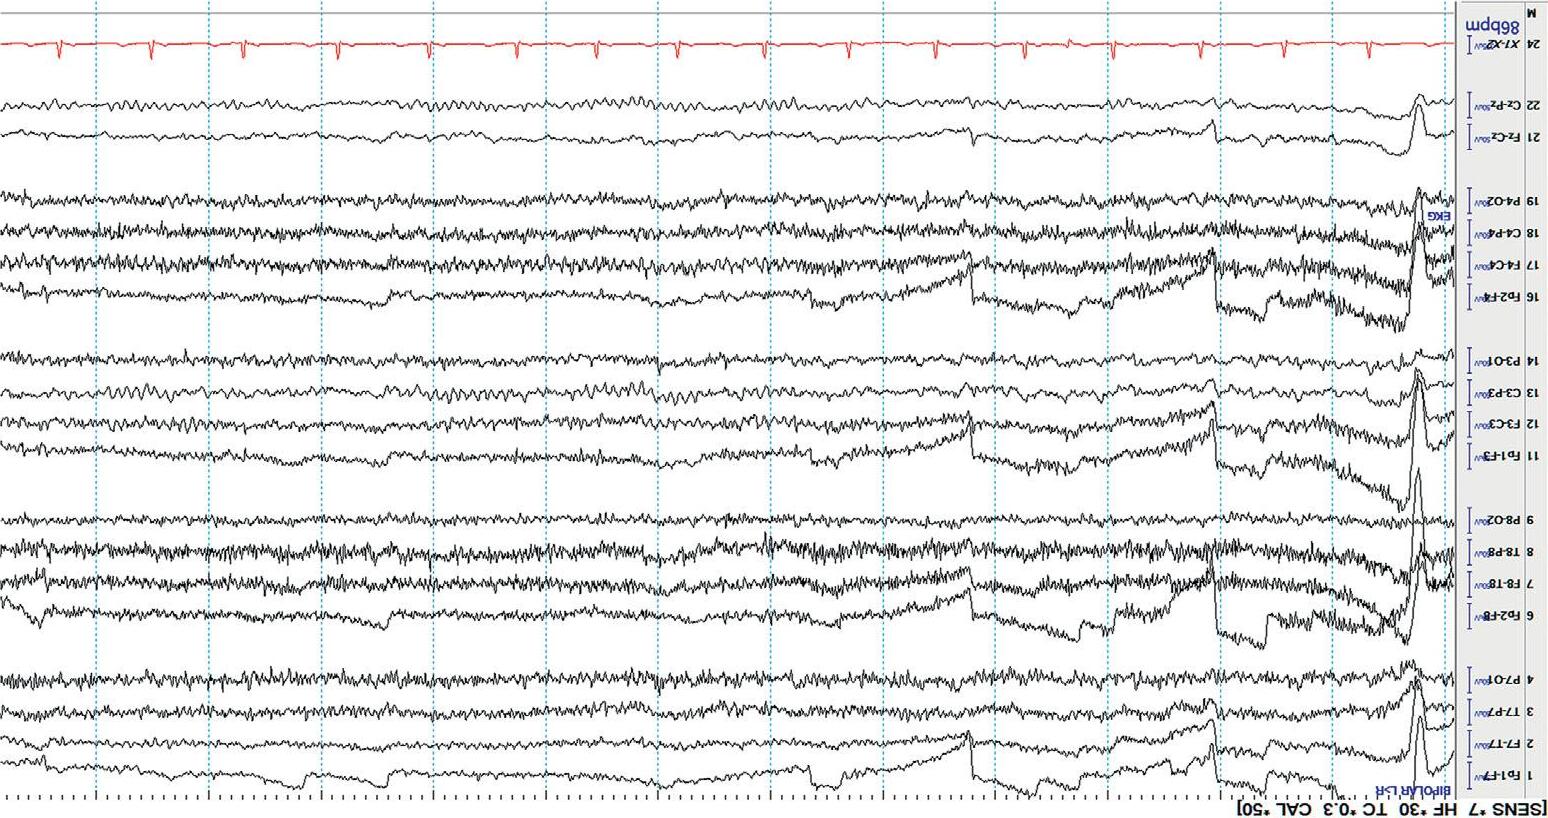

Mostdisplaysshow10or15secondsperpageofEEG. Figure1.5 showsa typicaldisplayusingthelongitudinalbipolarmontagewithexcessivemuscle artifactbefore(a)andafter(b)applicationof30Hzhighfrequencyfilter.

Figure1.5(a) EEGwithHFFsetto70Hz.

Figure1.5(b) ThesameEEGwithHFFsetto30Hz.